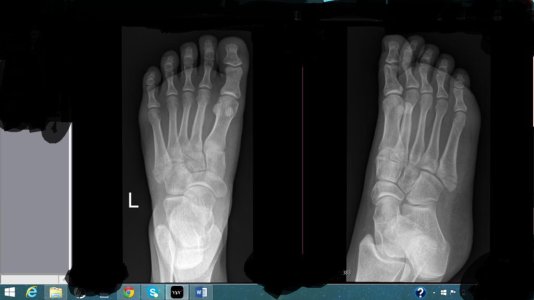

Здравствуйте, мне 19. Рост 150см вес 49, 2 недели назад играла фрисби и повернула ногу, думала ничего серьезного врач приходила сказала связки, спустя 1,5 недели пошла в больницу где мне сделали рентген и написали, что у меня перелом 5-ой плюсневой кости (это написано на польском перевела через переводчик), поставили гипс, сказали через недельку в другую больницу съездить. Сегодня друг забрал мой рентген, посмотрите пожалуйста, ничего серьезного, долго мне придется носить гипс, так как через 5 дней у меня поездка, можно мне ходить? иногда наступаю дома на ногу мне не больно ходить еще. Посмотреть вложение 12228